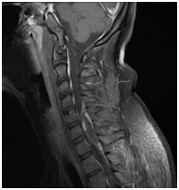

Ependimoma a gerincvelő. MR minta degeneratív változások a nyaki gerinc, a C5-C6 lemez extrudálás, C6-C7, C7-Th1.

T2VI T1 (kontraszt)